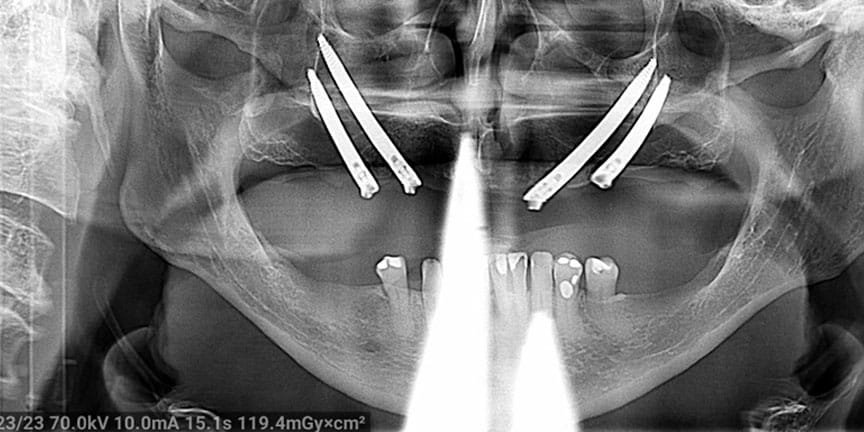

Expertise with Complex Cases: We handle challenging cases that other providers may struggle with, offering solutions where others cannot.